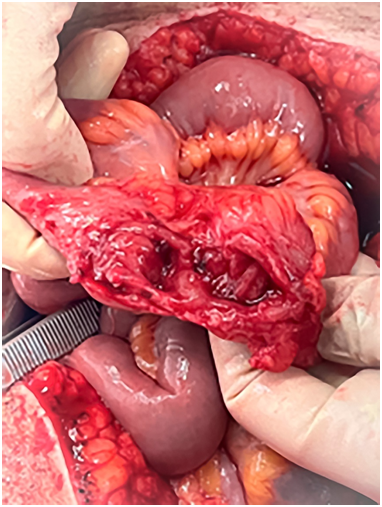

После операции состояние пациентки стабильное, мочеиспускание свободное, моча обычного цвета. Через 12 часов при удалении марлевого выпускника в рану поступило кишечное содержимое. Пациентка транспортирована в операционную. Выполнена нижнесрединная лапаротомия. В брюшной полости выраженный спаечный процесс. Висцеролиз. При ревизии выявлен щелевидный свищ подвздошной кишки в 20 см от илеоцекального перехода на 2/3 просвета с омозолелыми краями, плотно фиксированной в малом тазу (рис. 4). После его выделения обнаружен свищ дна мочевого пузыря до 2 см в диаметре (рис. 5).

Рис. 4. Интраоперационное фото: свищ подвздошной кишки

Fig. 4. Intraoperative view of fistula of the ileum